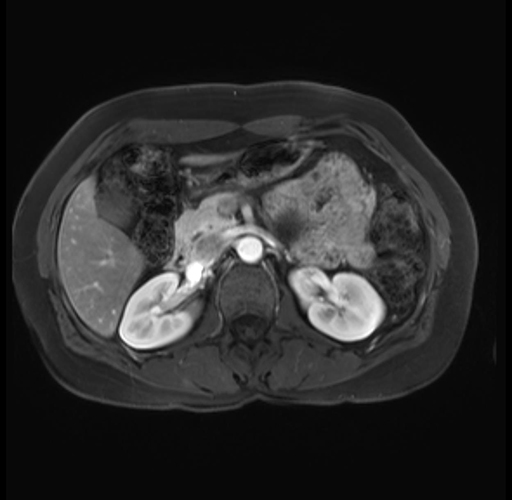

Imaging Analysis

Look through the patient's CT scan to identify any areas of concern for the necessary procedure.

Based on your CT findings, which issue(s) are present and would give reason for "planned slowing down moment(s)" in this case?

Considering a standard distal pancreatectomy procedure, what step(s) of the operation would you do differently in this case?